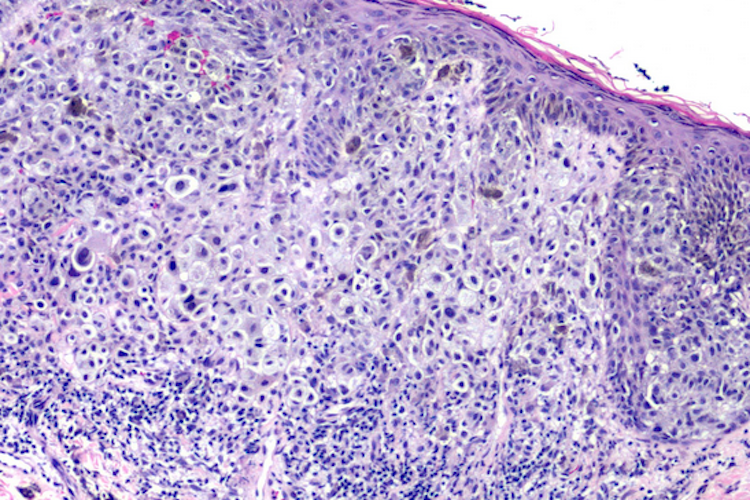

另外,除了可通过外观区分黑素细胞痣和黑色素瘤,也可通过病理组织学检查进行鉴别。在进行病理组织学检查时,可见黑素瘤细胞呈异型性,细胞大小、形态不一,胞核大,可见到核分裂及明显核仁,胞质内可含有色素颗粒,对多巴和酪氨酸酶呈强阳性反应。